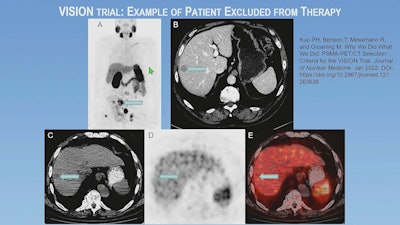

"If you've met one of these size criteria on CT, then you need to assess those lesions that met the type size criteria, and if even one of those lesions was PSMA-negative, which means uptake the same or less than liver, you're excluded from therapy," Kuo explained.

Ultimately, about 15% of patients were excluded from the randomization arm of the VISION trial due to the imaging criteria.